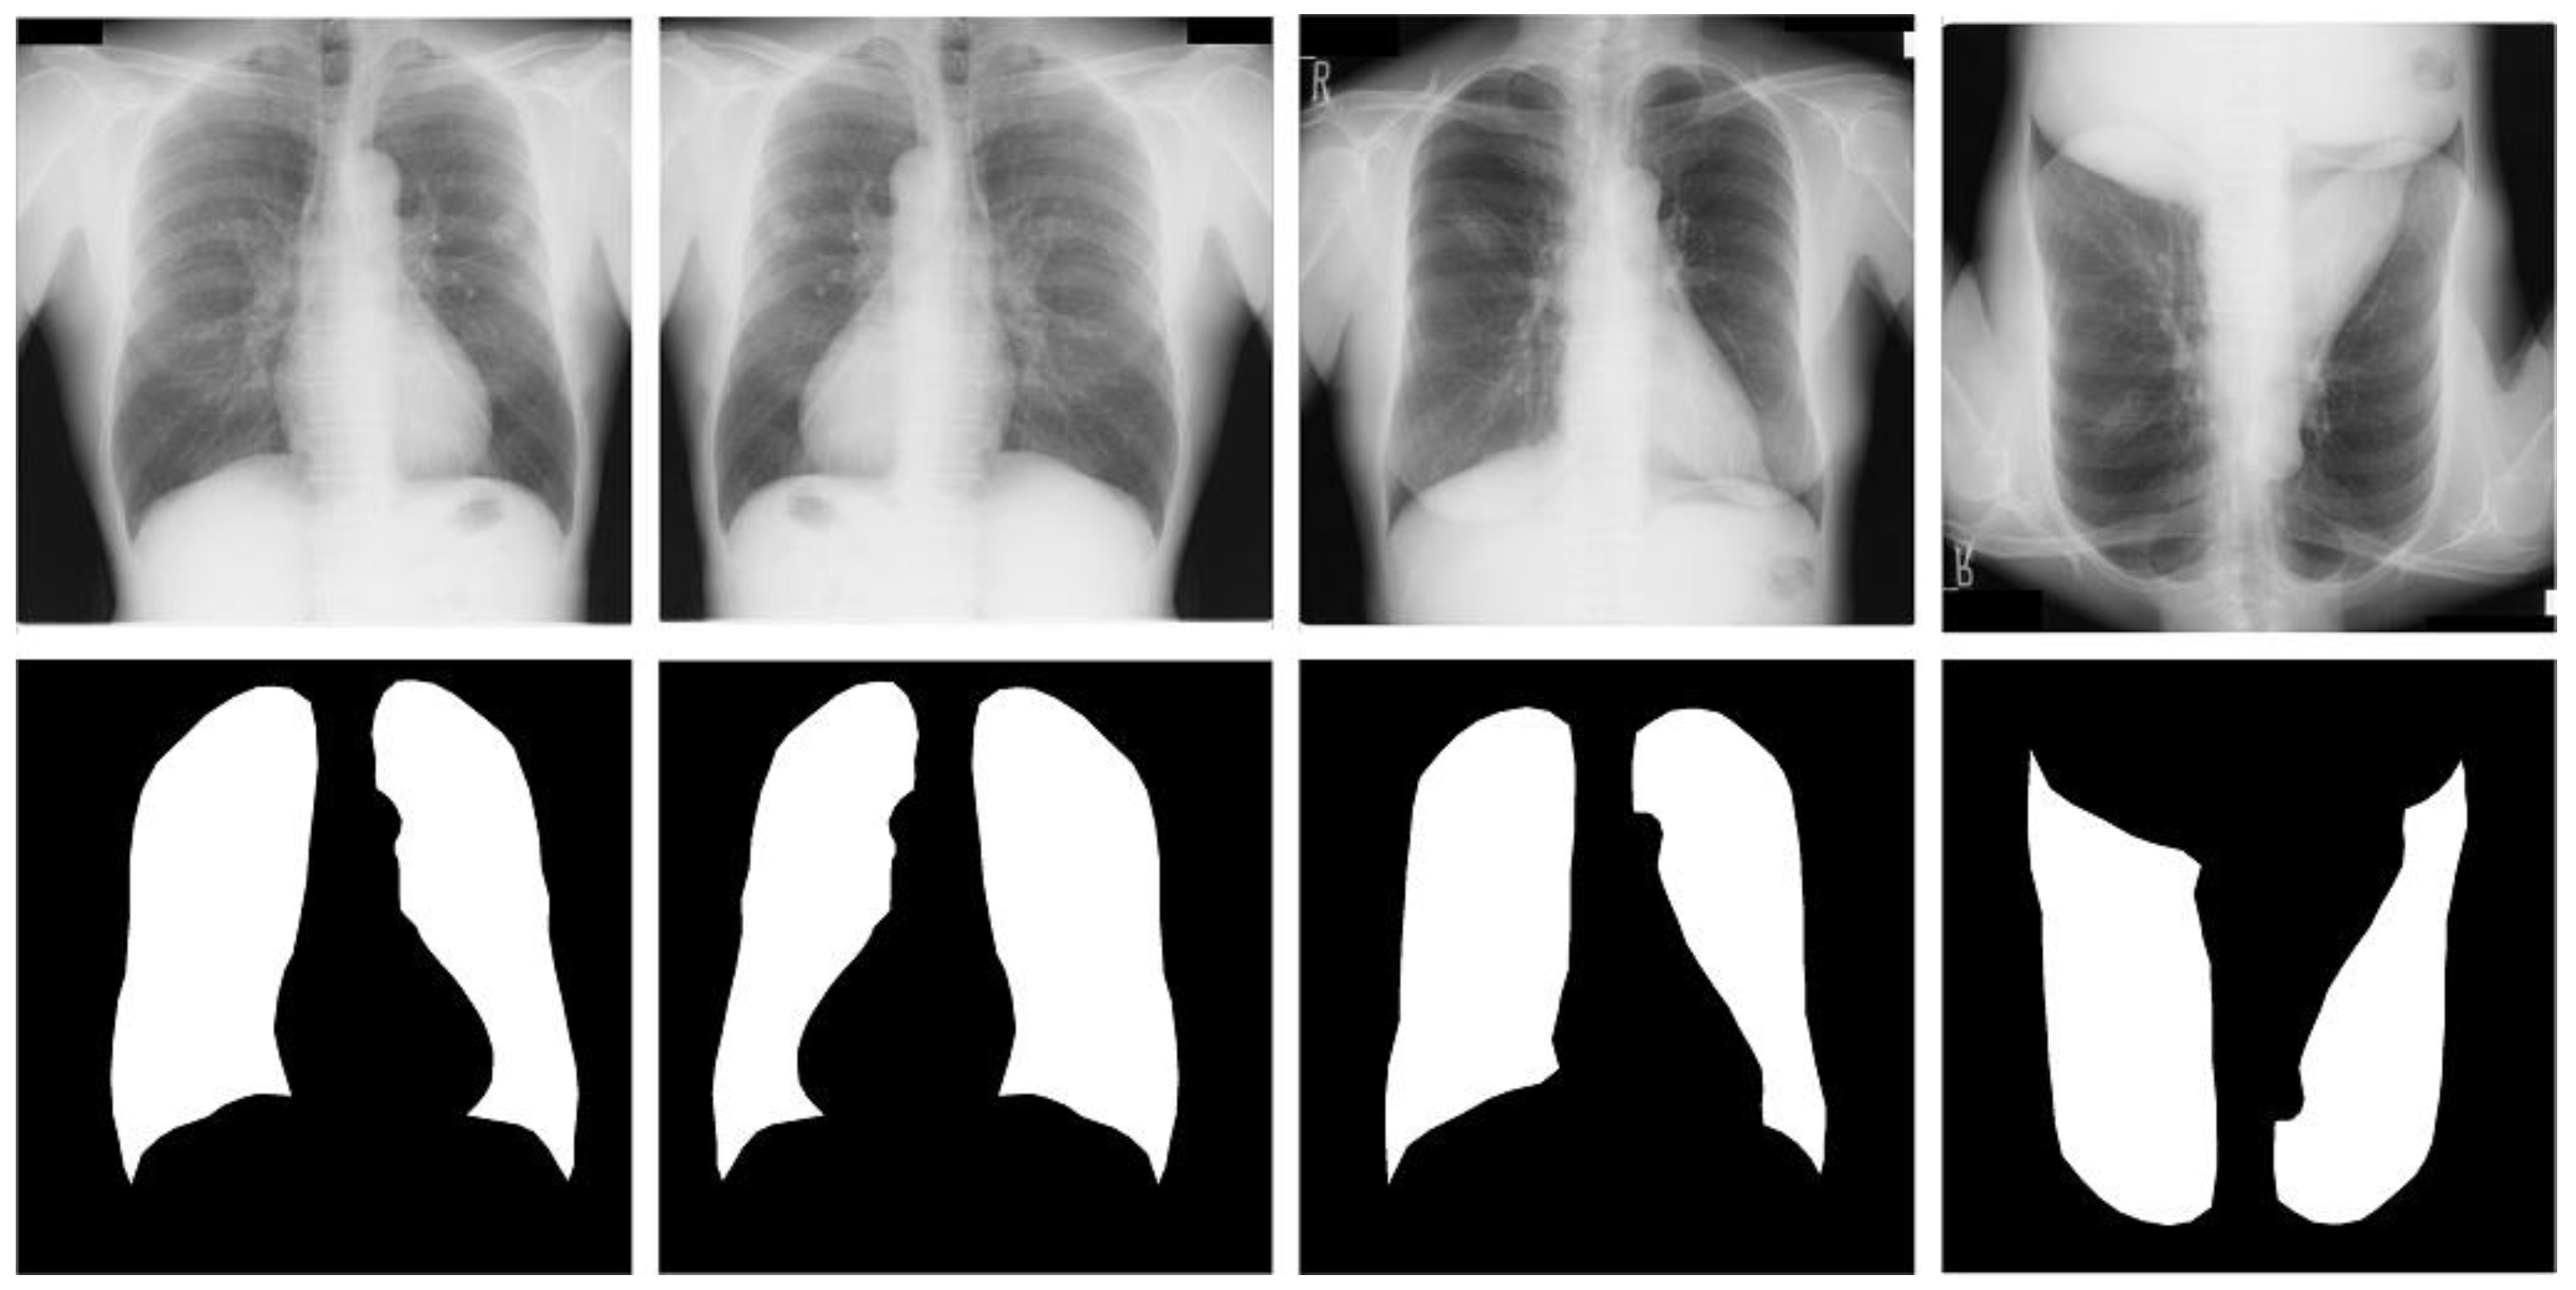

Shenzhen dataset [18]. This dataset is a collaboration between the Third People’s Hospital of Shenzhen, Guangdong, China, and the National Library of Medicine of Maryland, USA. It contains 662 radiographic images of the human chest region; each CXR radiograph is a single-channel grayscale image with a color depth of 8 and an average resolution of 326 radiographs healthy subjects and 336 from patients with tuberculosis. We used this dataset supervised and labeled by professional radiologists, which was provided by Jaeger et al. [18]. For the Shenzhen dataset, we used simple three-fold machine rotations and a simple three-fold flip data enhancement strategy, and trained the original image data together in the expanded dataset, which was expanded to seven times the original size, containing 4634 images. We use 3710 images as training cases, 336 images as validation cases, and 336 images as test cases. Table 1 shows the CXR and its specification summary of the X-ray film images of the three data sets after data enhancement, and the original and enhanced example images of the three data sets are shown in Figure 3, Figure 4 and Figure 5.

Figure 3.

Images and masks of the JSRT dataset.